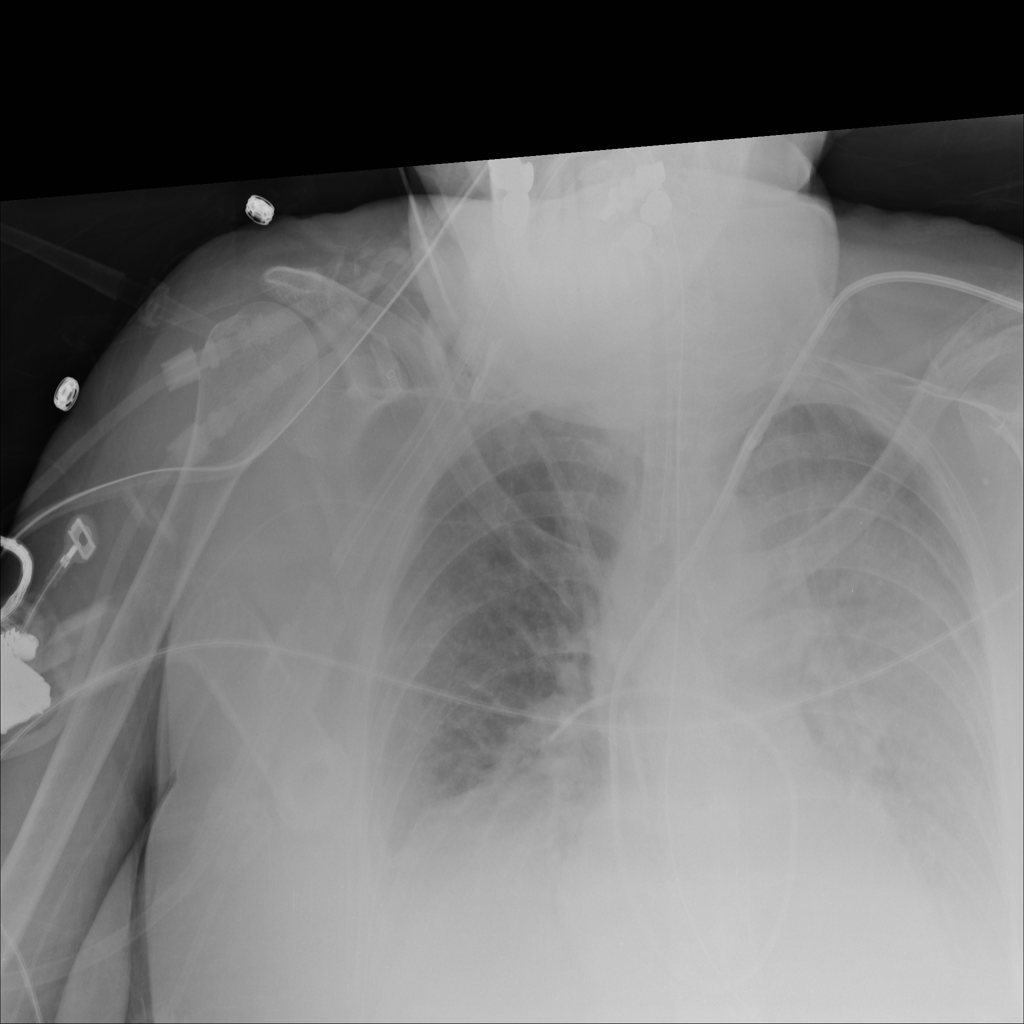

PAT-04B3 · IMG-001Consolidation

PAT-04B3 · IMG-001

PA